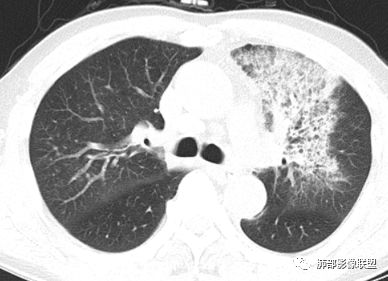

胸CT:左肺上叶前段实变,其周围及左肺上叶尖后段可见肺气肿背景下渗出性病变,病灶内可见支气管扩张,气道壁呈不规则增厚,双肺散在小结节状影;右肺下叶结节影,内可见空泡,边缘模糊,不规则。增强可见病灶内血管造影征,右肺门增大,纵隔淋巴结多发肿大。

左肺上叶大片混合网格磨玻璃影,边界清,边缘分叶膨隆,内支气管走行狭窄扩张,实变区边界清,上叶支气管管腔窄,心膈角淋巴结肿大,考虑肺炎型肺癌—腺癌。左肺下肺门结节,边缘膨隆,突入中间段及下叶支气管腔,背段支气管阻塞,周围少量小花小草,考虑鳞癌。右下叶外侧基底段结节,边缘有膨隆,有血管牵拉进入,上缘支气管贴边,考虑肺癌,性质?

薏米:老年男性,发热,咳嗽5天,胸痛2天,平素慢性咳嗽,咳痰10年,未系统诊治,基础糖尿病史,此次以急性发病为主,白细胞正常,CRP增高,IGE增高,CEA轻度增高,左肺上叶散在片状密度增高影,边界清楚,小叶间隔增厚,内有磨玻璃影,部分支气管壁增厚,部分有扩张,部分有近段粗细不均,少许气囊,右肺下叶可见一结节影,有凹陷,有膨隆,似有结节感,综合考虑左肺上叶考虑黏液性腺癌,鉴别曲霉,抗感染后复查:右肺下叶恶性。

患者中老年男性,发热,咳嗽5天,胸痛2天。慢性咳嗽,咳痰10余年,未目前出现活动后胸闷气短,有基础糖尿病、高血压病史,查白细胞正常,CRP增高,IGE增高,CEA轻度增高。胸部CT:左肺上叶片状密度增高影,边界清楚,内见小叶间隔增厚,呈蜂窝网格状,内有磨玻璃影,部分支气管壁增厚,部分有扩张,部分有近段粗细不均;右肺下叶可见一结节影,有凹陷,有膨隆,似有结节感。综合考虑恶性病变,腺癌可能大,鉴别结核。

老年男性,糖尿病病史,crp及ige明显增高,cea轻度增高。影像:左肺上叶前段网格状高密度影,部分实变,部分前段支气管走形僵直。右肺下叶背段近肺门处及右肺下叶外侧基底段各见一枚结节,可见浅分叶,外侧基底段结节可见空泡。纵隔多发淋巴结肿大。综合考虑:肺癌,粘液腺癌?

患者中老年男性,发热,咳嗽5天,胸痛2天。慢性咳嗽,咳痰10余年,目前出现活动后胸闷气短,有基础糖尿病、高血压病史,查白细胞正常,CRP增高,IGE增高,CEA轻度增高。胸部CT:左肺上叶片状密度增高影,边界清楚,内血管穿行,呈蜂窝网格状,内有磨玻璃影,部分支气管壁增厚,部分有扩张,部分有近段粗细不均;右肺下叶可见一结节影,有凹陷,有膨隆,似有结节感,右侧肺门淋巴结肿大,纵隔多发淋巴结肿大、部分伴有钙化。综合考虑恶性病变,左上肺粘液腺癌可能,右下肺小细胞癌?两源论考虑:左上肺粘液腺癌或粘膜相关性淋巴瘤?右下肺结核球伴肺门淋巴结肿。

老年男性,左肺上叶网格状ggo,边缘清晰,蜂窝状改变,支气管充气,走形僵直,远端扩张。右肺下叶结节影,浅分叶,边界清晰。纵隔多发淋巴结肿大并钙化。糖尿病,CRP.IGE增高,综合考虑:结核合并曲霉,鉴别粘液腺癌,淋巴瘤。

浪迹天涯:

左上肺大片状网格样高密度影,边缘清楚,支气管稍扩张,分布未沿支气管走形,增强后病灶稍强化(不知道是不是伪影),其内血管未见明显破坏,纵隔内多发淋巴结,考虑黏膜相关性淋巴瘤,粘液性腺癌待排。

实变区边缘收缩,部分区域紧贴纵隔胸膜。

胸膜下有间隙

左肺上叶病灶长轴与支气管走形一致,提示沿支气管分布病变,倾向于炎性,大家可能怀疑这个病例是来源于胸膜下为主的,胸膜下来源首先整体是来源于胸膜下,与胸膜下之间没有间隙,而这例与胸膜下有间隙。而且这个病变是沿支气管朝外蔓延的,而胸膜下来源的是朝内蔓延的,唯一给我们错觉的是靠近纵隔胸膜这个地方有问题。但是靠近纵隔胸膜这个位置实变不是靠近胸膜实变,它边缘收缩的,没有膨隆的迹象。我们看到里面支气管直达远端稍扩张,是以中央间质为主、小叶间隔朝外蔓延,有间质也有实质病变,走向是沿中央间质方向走的,我个人倾向炎性病变。    问题是右下叶病灶怎么解释?右隔上、右肺门各有一个结节。这个病人有急性咳嗽、胸痛的病史,还有糖尿病病史,周围渗出比较明显,应该警惕炎性病变,要警惕克雷伯杆菌、结核、金葡菌霉菌,因为糖尿病人经常好发这些病菌感染。那么右下叶病变怎么考虑?能不能一元论?    左肺病灶是一个急性渗出为主的病变,一个急性感染的迹象;右肺下叶背段结节,没有看到支气管,增强图支气管壁增厚,局部小结节,呈分叶状,支气管堵塞,没有粘液栓样指套样改变,但是里面有强化,我倾向于癌,其次待排结核。我还是倾向于癌的可能性,恶性可能性大一些,可惜我看不到支气管腔内。还考虑有没有淀粉样变性的问题,弥漫钙化灶最常见的一个是结核,另一个是淀粉样变性。叶段支气管壁有弥漫增厚的迹象。所以淀粉样变性跟结核都要考虑。

应该是阻塞性肺炎,抗感染后查PET CT的时候左上肺已经有部分吸收了。

鳞癌起源于支气管粘膜,是气道中最常见的恶性肿瘤,易造成支管壁增厚,并突入腔内形成结节,造成狭窄、阻塞或截断;早期鳞癌表现为沿支气管生长的梭形结节或局限性增厚,辖区内常出现阻塞性炎症,这样的病灶赢多平面重建并仔细观察支气管改变;如果有支气管壁偏心性增厚伴管腔狭窄或腔内结节形成,都要想到早期鳞癌的可能性,复查或内窥镜检查是必要的。

鳞癌好发于中老年人,与吸烟关系密切,如果发现不易吸收的,或同一部位反复无常局限性肺炎,我们应当仔细观察支气管壁的病变除外阻塞的可能;该病例右肺下叶背段及左肺上叶支气管有肿块及管壁的增厚,应当想到恶性可能。

2.左肺上叶大范围高密度影,几乎占据整个肺叶,没有体积改变,尽管小叶间隔显示明显,但初诊还是首先会想到社区肺炎,尤其是结合患者有发热及左侧胸痛的临床表现。

会是粘液腺癌吗?如此大范围,又在上叶,周围却未见向外飘散的结节影,难以想象。

3.我们都注意到患者左肺上叶支气管开口的改变,这种改变有可能会用常见的“肉芽肿性炎”或“分泌物”加以解释,因管腔内的隆起部分未能观察到强化,管壁外未见相应快影或结节影。

熟料问题恰恰出在这里!它没能引起完全阻塞,未能形成“S”形肺不张。

该病例非常值得我们警醒,忽略支气管管腔内的任何异常都可能大意失荆州!